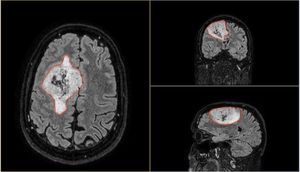

In the above image you can see my MRI scan. It's essentially an orthogonal view of my head, with each of the panels represents a different axis:

- Left panel: Top of my head (Axial view)

- Top right: Front to back of my head (Coronal view)

- Bottom left: Side of my head (Sagittal view)

The solid blue line you see in the views is the current plane I have selected to see. As you move this plane, all three images change accordingly. Notice how the blue line on the axial view (left panel) matches that of the coronal view (top right) in terms of position. The resulting image in the sagittal view (bottom left) is the image that corresponds with this selection I have made.

It's so incredibly clever and absolutely fascinating (to me at least)! I spent the best part of 2-3 hours looking at my own brain scans. I wish I knew what it all meant, but I plan on quizzing the experts when I get the chance. I'd like to write a blog post all about it in the future. So, watch this space!